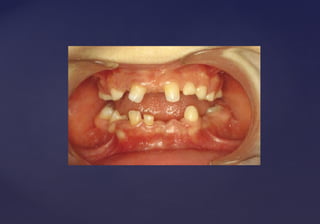

ANODONCIA VERDADERAANODONCIA VERDADERA



EEs la ausencia total de todos los dientes, ya sean temporarios os la ausencia total de todos los dientes, ya sean temporarios o

permanentes, lo que se llama “Anodoncia verdadera”, cuando faltan lospermanentes, lo que se llama “Anodoncia verdadera”, cuando faltan los

gérmenes de las piezas dentarias.gérmenes de las piezas dentarias.

 En los casos en que existen los gérmenes de las piezas dentarias y noEn los casos en que existen los gérmenes de las piezas dentarias y no

han hecho erupción, se habla de “Anodoncia falsa”han hecho erupción, se habla de “Anodoncia falsa”

 Suele estar asociada a un trastornó como la displasia ectodérmicaSuele estar asociada a un trastornó como la displasia ectodérmica

hereditaria, efectos de la radiación.hereditaria, efectos de la radiación.

 La forma mas frecuente de anodoncia es la parcial, los dientes ausentesLa forma mas frecuente de anodoncia es la parcial, los dientes ausentes

suelen ser los 3ros molares, incisivos laterales y 2dos premolaressuelen ser los 3ros molares, incisivos laterales y 2dos premolares